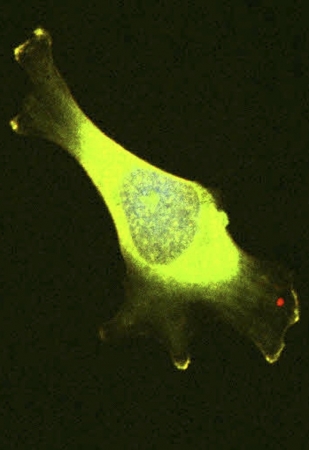

৪। লুক আই হ্যাভ লেগস

এটা ব্রেস্ট ক্যানসার সেল। যখন ক্যান্সার সেল মুভ করে তখন তারা ছোট ছোট 'পা' ( Filopodia )বের করে কোষের শরীর থেকে। এই 'পা' কিভাবে ডেভেলপ হয় তা দেখার জন্য আমরা গ্রিন কালার প্রোটিন দিয়ে ট্যাগ করে স্টাডি করি।

৫। On the Move

4 নং ছবির মতই একটি ব্রেস্ট ক্যান্সার কোষ। এটিও মুভ করার জন্য এরকম লম্বা 'পাখার মত পা' ডেভেলপ করে। আমরা যে প্রোটিন টা স্টাডি করি সেটা কে দেখা যাচ্ছে 'পায়ের' অগ্রভাগের অংশে কাজ করে (ঐ প্রোটিন এর সাথে গ্লো প্রোটিন লাগানো আছে, মাইক্রোস্কপে দেখার জন্য)